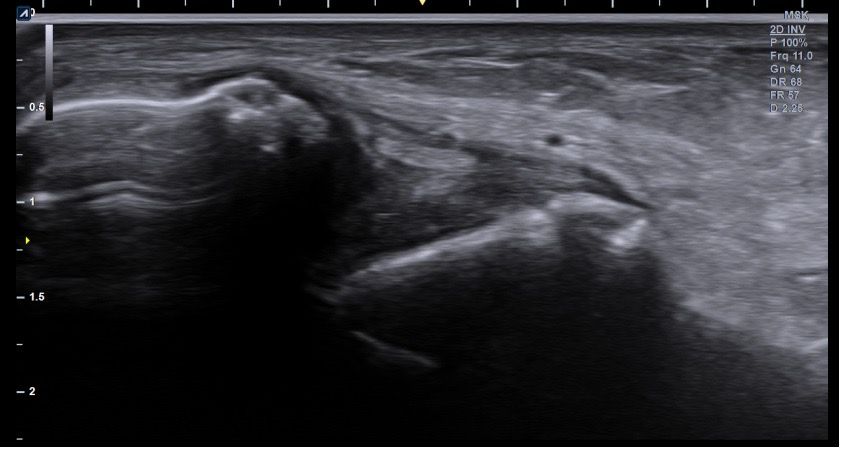

복숭아뼈 미세골절 초음파 사진 관련 질문

발목 접지른 후 치료받는 중인데요 복숭아뼈 미세골절이라고 하셨네요 3월 1일 다친뒤네 3월7일 병원방문후에 위에 초음파랑 엑스레이 촬영했고요 그뒤 반깁스 중입니다. 위에 엑스레이 상에선 안나오는데 초음파 사진에선 미세골절이 맞을까요? 골절이 경미한 수준인지 아니면 중한 건지 궁금합니다 그리고 다음주에 병원 방문 후 초음파 또 촬영하기로 했는데 그때 반깁스도 풀 수 있을까요??

• 2번 째 사진

발목의 복숭아뼈에 미세골절이 의심되는 경우, 엑스레이에서는 미세골절이 잘 보이지 않을 수 있습니다. 엑스레이는 큰 골절을 잘 확인하지만, 미세한 골절이나 염증 반응은 잘 나타나지 않기 때문이죠. 초음파는 조직의 변화를 보다 민감하게 감지할 수 있기 때문에, 미세골절을 발견하는 데 도움을 줄 수 있습니다. 초음파에서 미세골절이 확인되었다면, 이는 경미한 골절일 가능성이 높아요. 하지만 골절의 정확한 상태나 치유 과정을 판단하려면 정밀 검사가 필요하죠